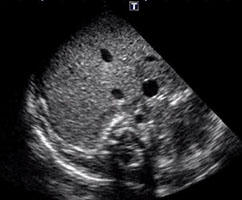

3、心エコー検査で心腔内腫瘤が認められた。合併しうる異常はどれか。2つ選べ。

- 虹彩結節

- 血管線維腫

- 脳内石灰化

- カフェ・オ・レ斑

- 三叉神経領域血管腫

正解:b, c